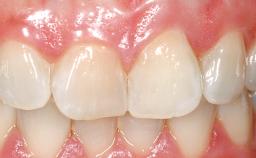

Immediate Placement of an Implant in a Maxillary Right Central Incisor Site

A 30-year-old female patient was referred to the office for the treatment of tooth 11. Her chief concern at the initial visit was to inquire, “Why is my tooth pink?” Upon clinical examination, it was determined that tooth 11 had a previous history of trauma and that the clinical crown had become noticeably pink in color as a result of internal resorption. This diagnosis was confirmed radiographically, indicating a large radiolucency involving the central and distal portions of the clinical crown. It was determined that restoration of this tooth was not possible, and that extraction was indicated. The presence of a mid-line diastema, which the patient wanted to reproduce, directed the treatment plan for tooth replacement utilizing a dental implant.

| Esthetic Risk | High |

| Soft Tissue Contour and Volume | Ideal |